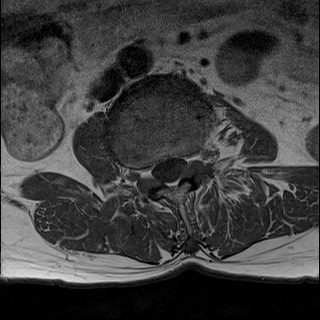

Ӵϲ ɿ ô ô 㸮 ٸ ̾ϴ. ϵ Ͻð ܻ 㸮 20⵿ ͽϴ. mri ˻ ɿ Ȳ ʹ ؼ Ȳ̶ ߽ϴ. ϻȰ ϰ 鼭 ½ϴ. ̴ ø鼭 Ͻô Ȳ ̷ ġ ص ȸ ϴ. δ Ҵµ, ù ȸԲ ˷ֽ ϰ β ϰ, ˷ֽ ü ƮĪ ϸ鼭 ȭǸ鼭 Ӵϲ ȸų ְ ǰ, β 鼭 ʴ β ؾϴ ŷο 1ϸ ijħ ڸ ǥ Ʈ ߽ϴ. ȸ ȭϽø鼭 Ϸ簡 ٸ ȸǽð 4ְ Ǿ Ǯ鼭 ¦ ҽϴ. ħ ȸ ȭϸ鼭 ڼ ü ƮĪ ϴ. ȥڼ Ͻʴϴ. ٳø鼭 ó Ͻ ʴϴ. ̾ ְ ̳ ߵ ʰ ϴ ȸԲ Ͻʴϴ. ʹ ϸ鼭 ϴ. Ȩ - ϱ ٴ Ȳ MRIԴϴ. |